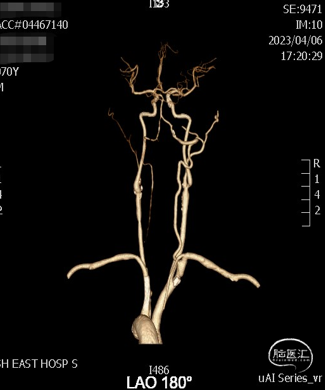

②术前颈动脉CTA:左侧锁骨下动脉支架置入术后状态,腔内未见明显狭窄;左侧椎动脉起始部闭塞;右侧椎动脉V4段重度狭窄;右侧颈内动脉起始部重度狭窄。

右侧椎动脉V4段重度狭窄伴斑块形成。

术前影像

脑血管造影DSA:

右侧椎动脉V4段重度狭窄,并向对侧椎动脉返流。